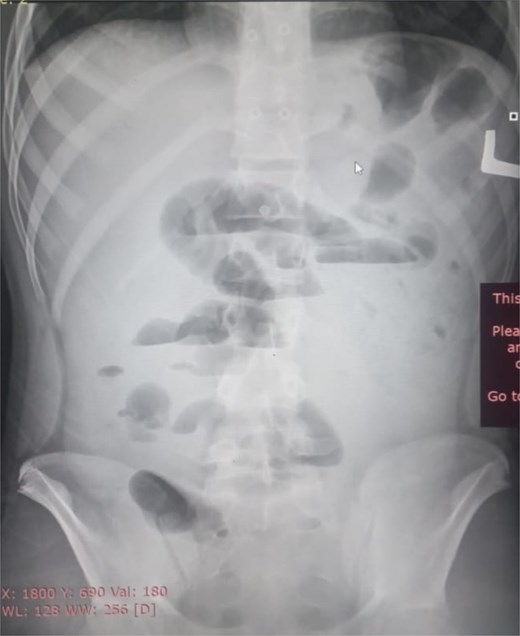

Initial radiographic evaluation with a plain abdominal X-ray confirmed the clinical suspicion of acute intestinal obstruction, demonstrating multiple air-fluid levels and diffuse small bowel dilatation (Fig. 1). To further delineate the underlying etiology, a contrast-enhanced computed tomography (CECT) scan was performed; providing critical diagnostic information it revealed, in the right iliac fossa, a striking encapsulation of the small intestine loops within a sac-like membrane, accompanied by ascites. This constellation of findings formed a pathognomonic cocoon-like structure (Fig. 2). Furthermore, the CECT identified a concurrent gut malrotation, evidenced by a left-sided displacement of the colon (Fig. 3). Laboratory findings showed an elevated total leukocyte count (TLC) of 21 000, indicative of inflammation, while other parameters were within normal limits. The patient underwent an exploratory laparotomy. Intraoperatively, the abdominal viscera were encased within a thick fibrous membrane (Fig. 4), containing ascitic fluid. The membrane was incised, adhesiolysis was performed, and the entrapped small bowel loops were released, and then a kink in the small intestine causing obstruction was identified and corrected. Additionally, the appendix was found to be secondarily involved in the encapsulating process. It was encased in the dense fibrocollagenous membrane, forming an inflammatory mass consistent with chronic serositis and localized fibrosis, rather than a classic acute appendicular phlegmon. Based on this intraoperative assessment that the mass was a manifestation of the cocoon’s chronic inflammation, a simple appendectomy was performed instead of a more extensive right hemicolectomy. This procedure was necessary to achieve complete release of the entrapped bowel, remove this localized inflammatory focus, and obtain a specimen for histopathology to definitively rule out a primary appendiceal pathology as a secondary cause of the peritonitis. Furthermore, ascitic fluid analysis showed no bacterial or mycobacterial growth, ruling out tuberculosis and the histopathological examination confirmed the fibrocollagenous nature of the membrane. The patient recovered well postoperatively and was discharged on the sixth day with advice for a follow-up after 2 weeks. At the follow-up visit, he reported no symptoms, and abdominal imaging confirmed the absence of obstruction. Histology further confirmed the benign fibrous nature of the membrane, with no signs of malignancy.

Abnormal positioning of encapsulated small bowel. This axial CT view, taken at a lower abdominal level, illustrates the profound anatomical derangement. The entire cluster of small bowel loops is seen encased and displaced into the right iliac fossa, a finding consistent with the combined effects of the cocoon membrane and the patient’s gut malrotation.